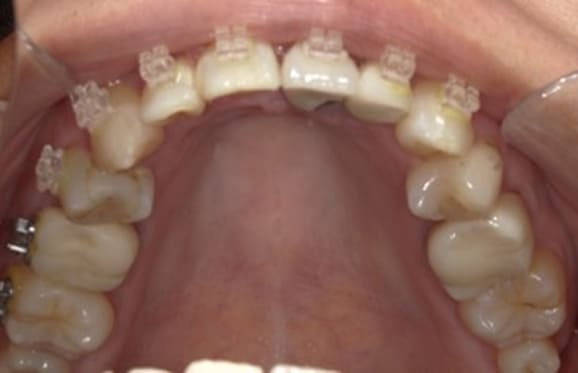

クリアブラケットを選択された患者様はホワイトワイヤーと透明ゴムを使用することで、見た目が目立ちにくくなります。また、各色カラーゴムもご用意しており、追加料金はかからずに選んでいただけます。

藤沢デンタルオフィスのワイヤー矯正 藤沢デンタルオフィスのワイヤー矯正